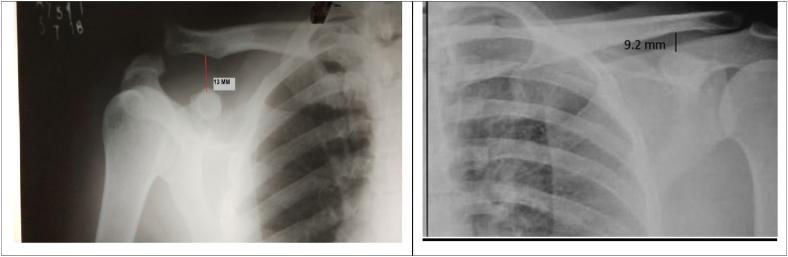

The average age of patients was 31 yrs. RTPCR test for COVID-19 was negative in all patients. Median surgical time was 25 min (Interquartile Range[IQR] = 16-34 min) and median follow-up duration was 36 weeks (IQR = 33-39 weeks). Median visual analogue scale score and IQR at pre-operative, 3 month, 6 month and 9 month follow-up was 7(IQR = 6-8), 3.5(IQR = 2.5-4.5), 2(IQR = 0) and 1(IQR = 0), respectively. Median constant score at pre-operative, 3 month, 6 month and 9 month follow-up were 34(IQR = 25-43), 65.5(IQR = 60.5-70.5), 82.5(IQR = 77.5-87.5) and 88(IQR = 81-95). There was significant improvement in clinical status (non parametric-Friedman test p < 0.001). Radiographs showed no loss of reduction, fracture or implant failure till last follow-up.

患者的平均年龄为31岁。所有患者的新冠病毒RTPCR检测均为阴性。中位手术时间为25分钟(四分位间距[IQR]=16 - 34分钟),中位随访时间为36周(IQR=33 - 39周)。术前、术后3个月、6个月和9个月随访时的中位视觉模拟评分及IQR分别为7(IQR=6 - 8)、3.5(IQR=2.5 - 4.5)、2(IQR=0)和1(IQR=0)。术前、术后3个月、6个月和9个月随访时的中位Constant评分分别为34(IQR=25 - 43)、65.5(IQR=60.5 - 70.5)、82.5(IQR=77.5 - 87.5)和88(IQR=81 -